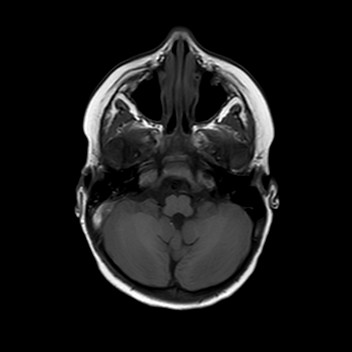

Esegue quindi una TAC che mostra una frattura

dell’osso occipitale con la presenza di un ematoma epidurale

di circa 9 mm adiacente al seno sigmoideo di destra.

La bambina inizia quindi terapia con enoxaparina alla dose di 1700 UI x 2/die con aggiunta di terapia antibiotica con ampicillina-sulbactam per profilassi. Nei giorni successivi Teresa è stata bene, l’instabilità è andata progressivamente scomparendo senza vomito o cefalea. I successivi controlli all’angio-RM e alla TAC hanno mostrato un rallentamento del flusso in seno sigmoideo destro con tumefazione e netta iperdensità dello stesso, che sono andati progressivamente scomparendo con solo una minima falda ematica residua al giorno della dimissione, dieci giorni dopo il trauma. La terapia è stata dimezzata e poi interrotta dopo tre settimane dall’avvio.

La presenza di atassia alla marcia con vomito è un segno tipico della trombosi del seno sigmoideo che, per quanto rara nel bambino dopo un trauma, va esclusa con una angio-RM, non essendo la TAC in grado di visualizzare chiaramente il flusso nei seni venosi, soprattutto se all’immagine si sovrappone la contestuale presenza di un ematoma. Inoltre la progressione dei sintomi neurologici indicava il trattamento del trombo con eparina, a differenza dei casi asintomatici dove è indicata la semplice reidratazione per evitarne la progressione e lo sviluppo di ipertensione endocranica.